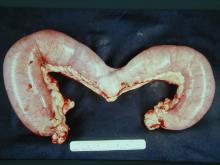

以上三個病例皆由超音波確診後,進行外科切除,手術取下之子宮外觀如下: 病例一:

子宮體及兩側子宮角膨大(圖1),子宮角切開可見腔內充滿血樣、膿樣分泌物,子宮內膜水腫,子宮內膜腺體囊腫性增生(圖2),子宮重量0.3 公斤。 病例二:

子宮體及兩側子宮角明顯膨大,子宮角切開可見腔內充滿黃色膿性分泌物,子宮內膜輕微糜爛,子宮重量1.9公斤。 病例三:

子宮體及子宮角明顯膨大,尤其靠兩側子宮角之前1/2段膨大更為明顯(圖5),子宮角切開可見血樣、膿樣分泌物,子宮壁明顯變薄,子宮內膜表面瀰漫散佈點狀火山口樣之潰瘍灶(圖6),子宮重量4.2公斤。 三、 組織病變: 病例一: